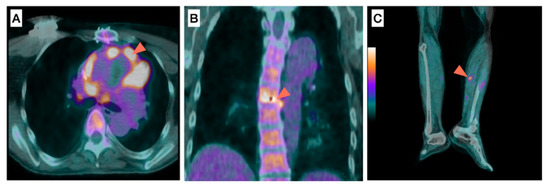

- Mikail, N.; Benali, K.; Ou, P.; Slama, J.; Hyafil, F.; Le Guludec, D.; Rouzet, F. Detection of Mycotic Aneurysms of Lower Limbs by Whole-Body (18)F-FDG-PET. JACC Cardiovasc. Imaging 2015, 8, 859–862. [Google Scholar] [CrossRef]